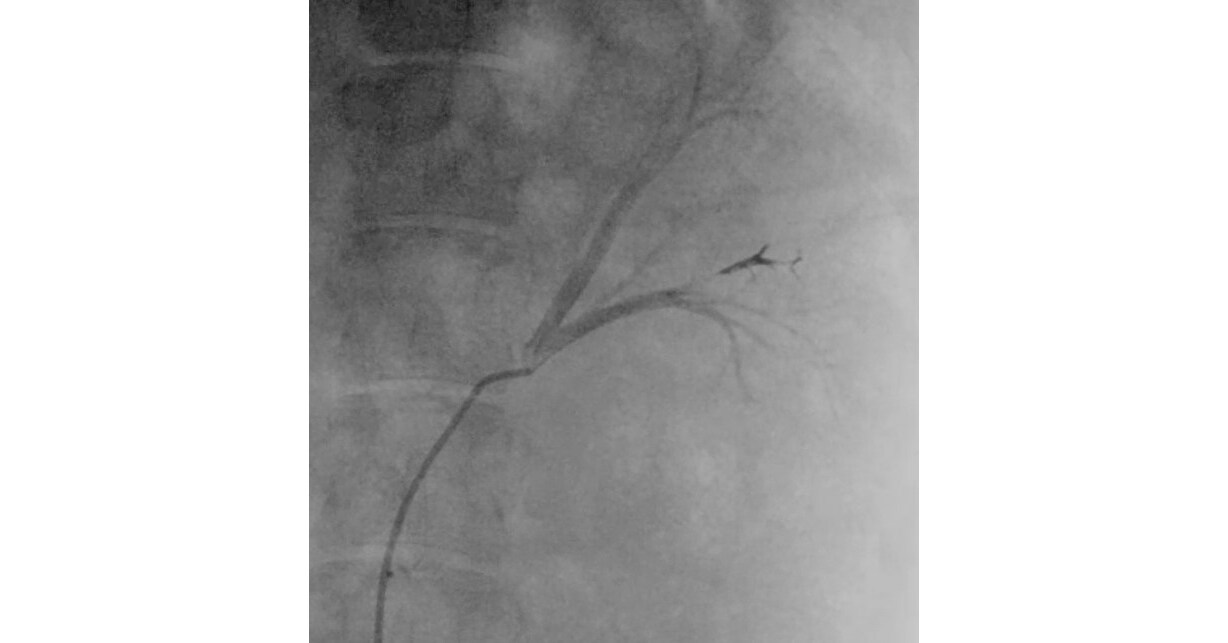

Hence then, the article about fluidx medical reveals new embolic platform for internal bleeding tumor treatment and other uses was published today ( ) and is available on PR Newswire ( Middle East ) The editorial team at PressBee has edited and verified it, and it may have been modified, fully republished, or quoted. You can read and follow the updates of this news or article from its original source.